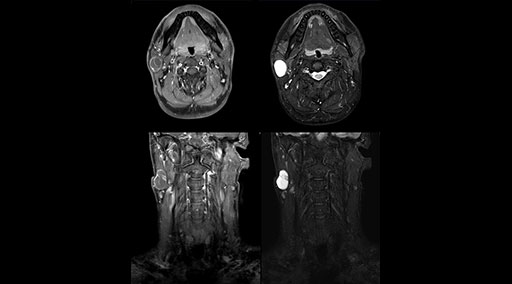

“Our DMG Lisle location includes a cancer center, so soft tissue neck scans, brachial plexus scans, and prostate scans are common. For these exams, mDIXON TSE provides excellent images with and without fat suppression all while helping us reduce repeats and work more efficiently,” Mr. Duffy says.

“With the 2-echo Philips mDIXON TSE the timing is short and the fatsat is very robust. The biggest thing is that you know your fat suppression will be good, even in thin patients or large patients that are off-center,” Mr. Sybesma says.

“mDIXON TSE raises our diagnostic confidence with its homogeneous

fat suppression. Neck exams and rheumatology patients are two examples where mDIXON TSE is especially useful,” Dr. Kaakaji says. “For us it’s also an efficiency boost in exams where we need pre and post T1-weighted images with great fat suppression.”